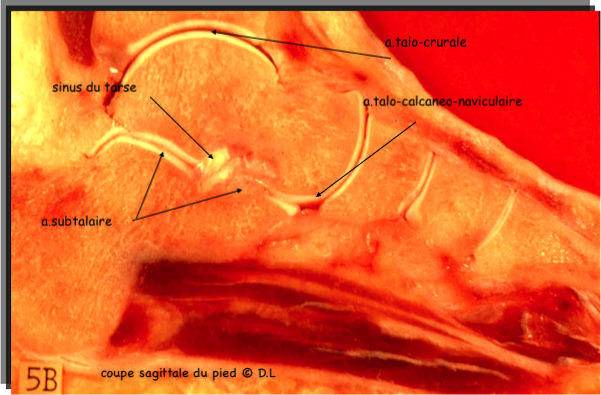

oppose la face distale du talus et la face proximale du calcaneus sur lequel le premier est posé, par le biais de deux surfaces articulaires distinctes séparées par un canal, le sinus du tarse.

Entre les deux se forme un canal osseux, le sinus du tarse, tunnel oblique en ventral et latéral, où se fixe le ligament interosseux (en haie) fait de deux insertions parallèles sur chacun des deux os.

Les deux surfaces ont leur propre capsule, celle de l'articulation talo calcanéenne ventrale étant commune avec l'articulation talo naviculaire.